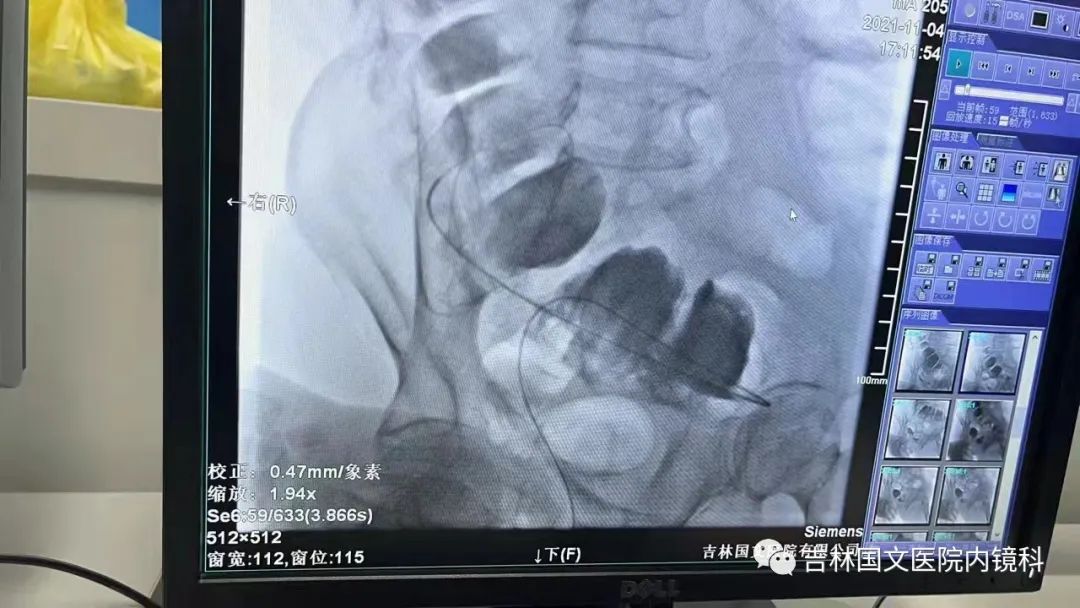

腸道支架置入

這是一位腸癌的患者,腫物生長(zhǎng)在乙狀結(jié)腸,將腸腔堵得只剩一個(gè)小孔,糞便自然很難通過(guò),腸梗阻的癥狀使患者十分難受,已多天未排氣排便,患者十分瘦削,開(kāi)始侯主任未借助任何工具探查一番,結(jié)果就是腸道太迂曲了,實(shí)在無(wú)法順利將導(dǎo)絲置入,通過(guò)邢主任使用腸鏡在前面引路一直到達(dá)病變部位,這時(shí)候侯主任將帶有外套管的導(dǎo)絲從活檢口插入,外套管抵在小孔處,導(dǎo)絲順利進(jìn)入,第一步成功。第二步就是將支架順著導(dǎo)絲送入指定位置,又是一大難關(guān),導(dǎo)絲十分軟,缺乏支撐力,腸道的彎曲十分陡峭,一用力支架抵在腸道低處,患者痛感極強(qiáng),只能另想辦法,嘗試多次后,在兩位主任的豐富經(jīng)驗(yàn)和堅(jiān)持不懈的努力下,支架順利置入,為患者解除了痛苦。